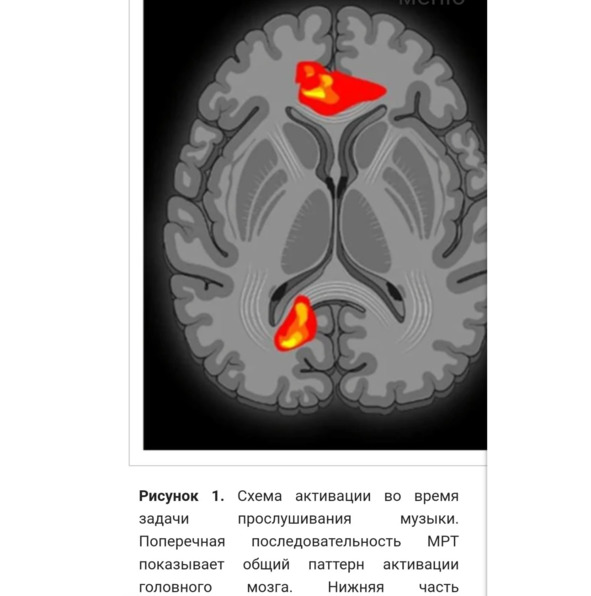

«При слушании музыки – большая активность в гамма-, бета- и альфа- диапазона. (1) гамма- активность как аффективную реакцию и сознательное распознавание предпочитаемой музыки; (2) бета-активность как оценка темпа предпочитаемой музыки и эмоциональное возбуждение, связанное с предпочтением; (3) альфа- активность как усиление внимания к когнитивным функциям, таким как восстановление памяти; и (4) усиленная синхронизация в альфа- диапазоне у танцоров, обусловленная воображением движений или творческим мышлением в целом. Музыкальная подготовка не оказывает существенного влияния на степень восприятия грува при прослушивании музыки/ритмов с высоким или низким ритмом или шума» (Stupacher et al., 2013, Witek et al., 2014). «Обучение танцам и музыке влияет на слуховую обработку, включая изменения в нейронной активности, связанные с конкретными музыкальными событиями, а также на синхронизацию различных частотных диапазонов мозговых волн (тета, альфа, бета и гамма) на разных электродах на коже головы» («Нейронаука танца…").

Музыка активизирует

Лимбическая система, особенно миндалевидное тело и гиппокамп, активируются.